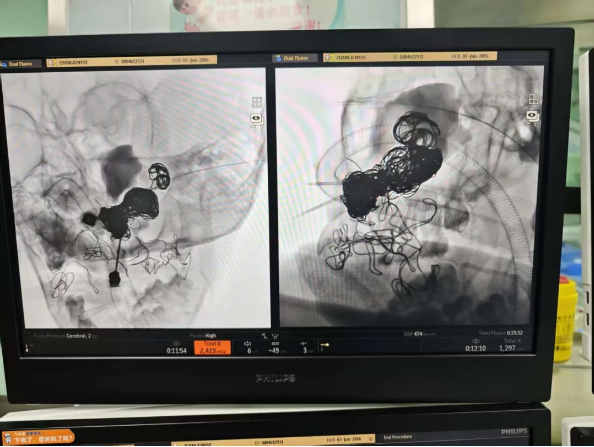

面对患儿危急的病情,申刚凭借精湛娴熟的专业技术、丰富扎实的临床经验,精准定位并穿刺上颌骨骨内瘤巢。在DSA(数字减影血管造影)设备的精准引导下,畸形血管团的位置、大小、形态及供血动脉清晰呈现。申刚小心翼翼地通过微导管将栓塞材料精准注入畸形血管团,循序渐进地阻断异常血流通道,每一个操作都精准无误、稳扎稳打,全程不敢有丝毫懈怠。经过近5个小时的奋力攻坚,在申刚团队与北京儿童医院口腔科于国霞团队共同努力下,手术于当日8时50分顺利完成,成功将患儿从死神的边缘拉了回来,手术过程顺利、效果显著,得到了北京儿童医院医护团队的高度认可与赞扬。

DSA(数字减影血管造影):显示畸形血管团块、扩张供血动脉及提前显影的回流静脉,是诊断“金标准”。